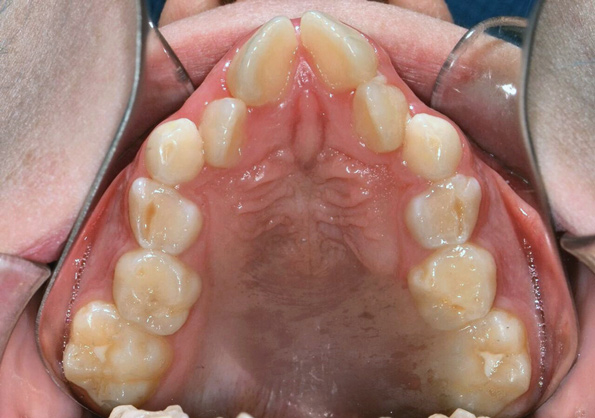

Fig 1. Functional shift in centric occlusion.

Figure 1

Fig 2. Functional shift in centric relation.

Figure 2

A common developmental abnormality is a localized anterior crossbite on permanent incisors, which may lead to trauma to these teeth. The most common cause of localized incisor crossbite is an anterior occlusal interference, which causes a functional shift when the patient moves from centric relation to centric occlusion (Figure 1 and Figure 2). This is not a true class III malocclusion, and proper diagnosis is critical to select the correct treatment. Sometimes this bite relationship is called a pseudo-class III relationship.2 Intervention in these cases is important because these teeth are at higher risk for recession, periodontal damage, and incisal chipping. Limited anterior braces and sometimes a palatal expander may be used to place the maxillary incisors facial to the mandibular incisors; this is referred to as "jumping the bite."